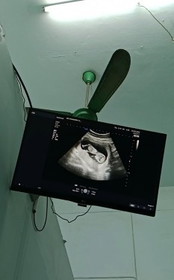

สวัสดีค้าบ รูปนี้คือซาว12week แต่คุณหมอบอกแอบเห็นจู๋นิดๆ แม่ๆมาอวดรูปซาวกัน❤️❤️❤️❤️ #ขอบคุณสำหรับคำคอมเม้นล่วงหน้าค่ะ #ท้อง2

12+2Wค่ะ หมอนัดวันนี้ถามคุณหมอว่ารู้เพศยังหมอบอกว่ายังค่ะ แม่ๆๆๆคนให้พอเดาได้บ้างค่ะ

12W5dค่ะหมอว่าน้องเป็นผู้หญิง รอลุ้นผลนิฟอีกทีค่ะ 🥰

14 wค่าาา คุณพ่อเค้าถ่ายไว้ บ้านนี้ได้ลูกสาวค่าา